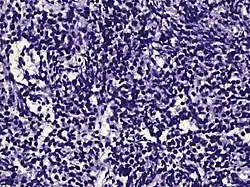

| Small-cell carcinoma | 0.3–2%[14][15][notes 1] |

|

Half of cases have usual acinar components[1] |

||||